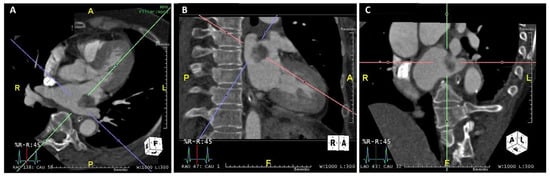

2. Case Presentation